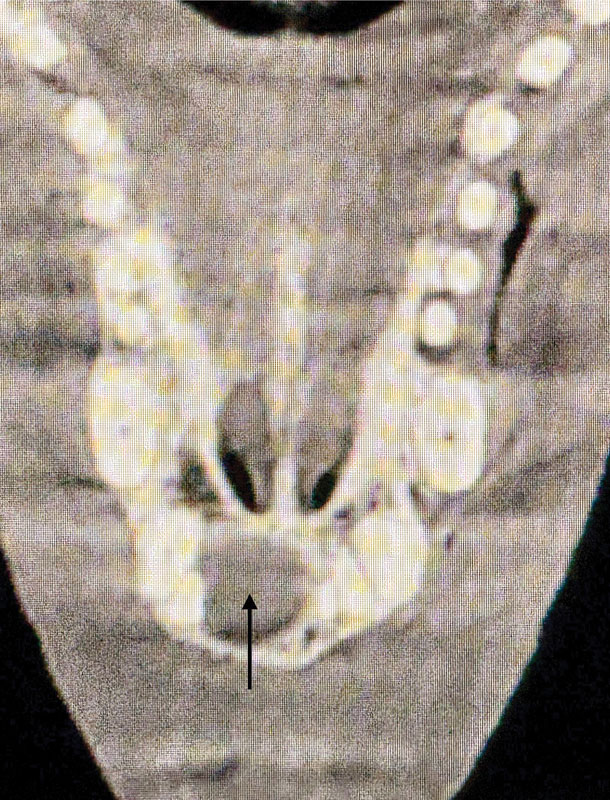

A cone-beam CT scan supported the cyst diagnosis as evidenced by an increased density of bone (cortication) immediately adjacent to the cystic structure (Figure 2).

A CT scan image of a canine patient.

Figure 2. Cone-beam CT scan of the maxilla showed a spherical cyst-like lesion with cortication and expansion toward adjacent incisor teeth. Photo courtesy Dr. John R. Lewis